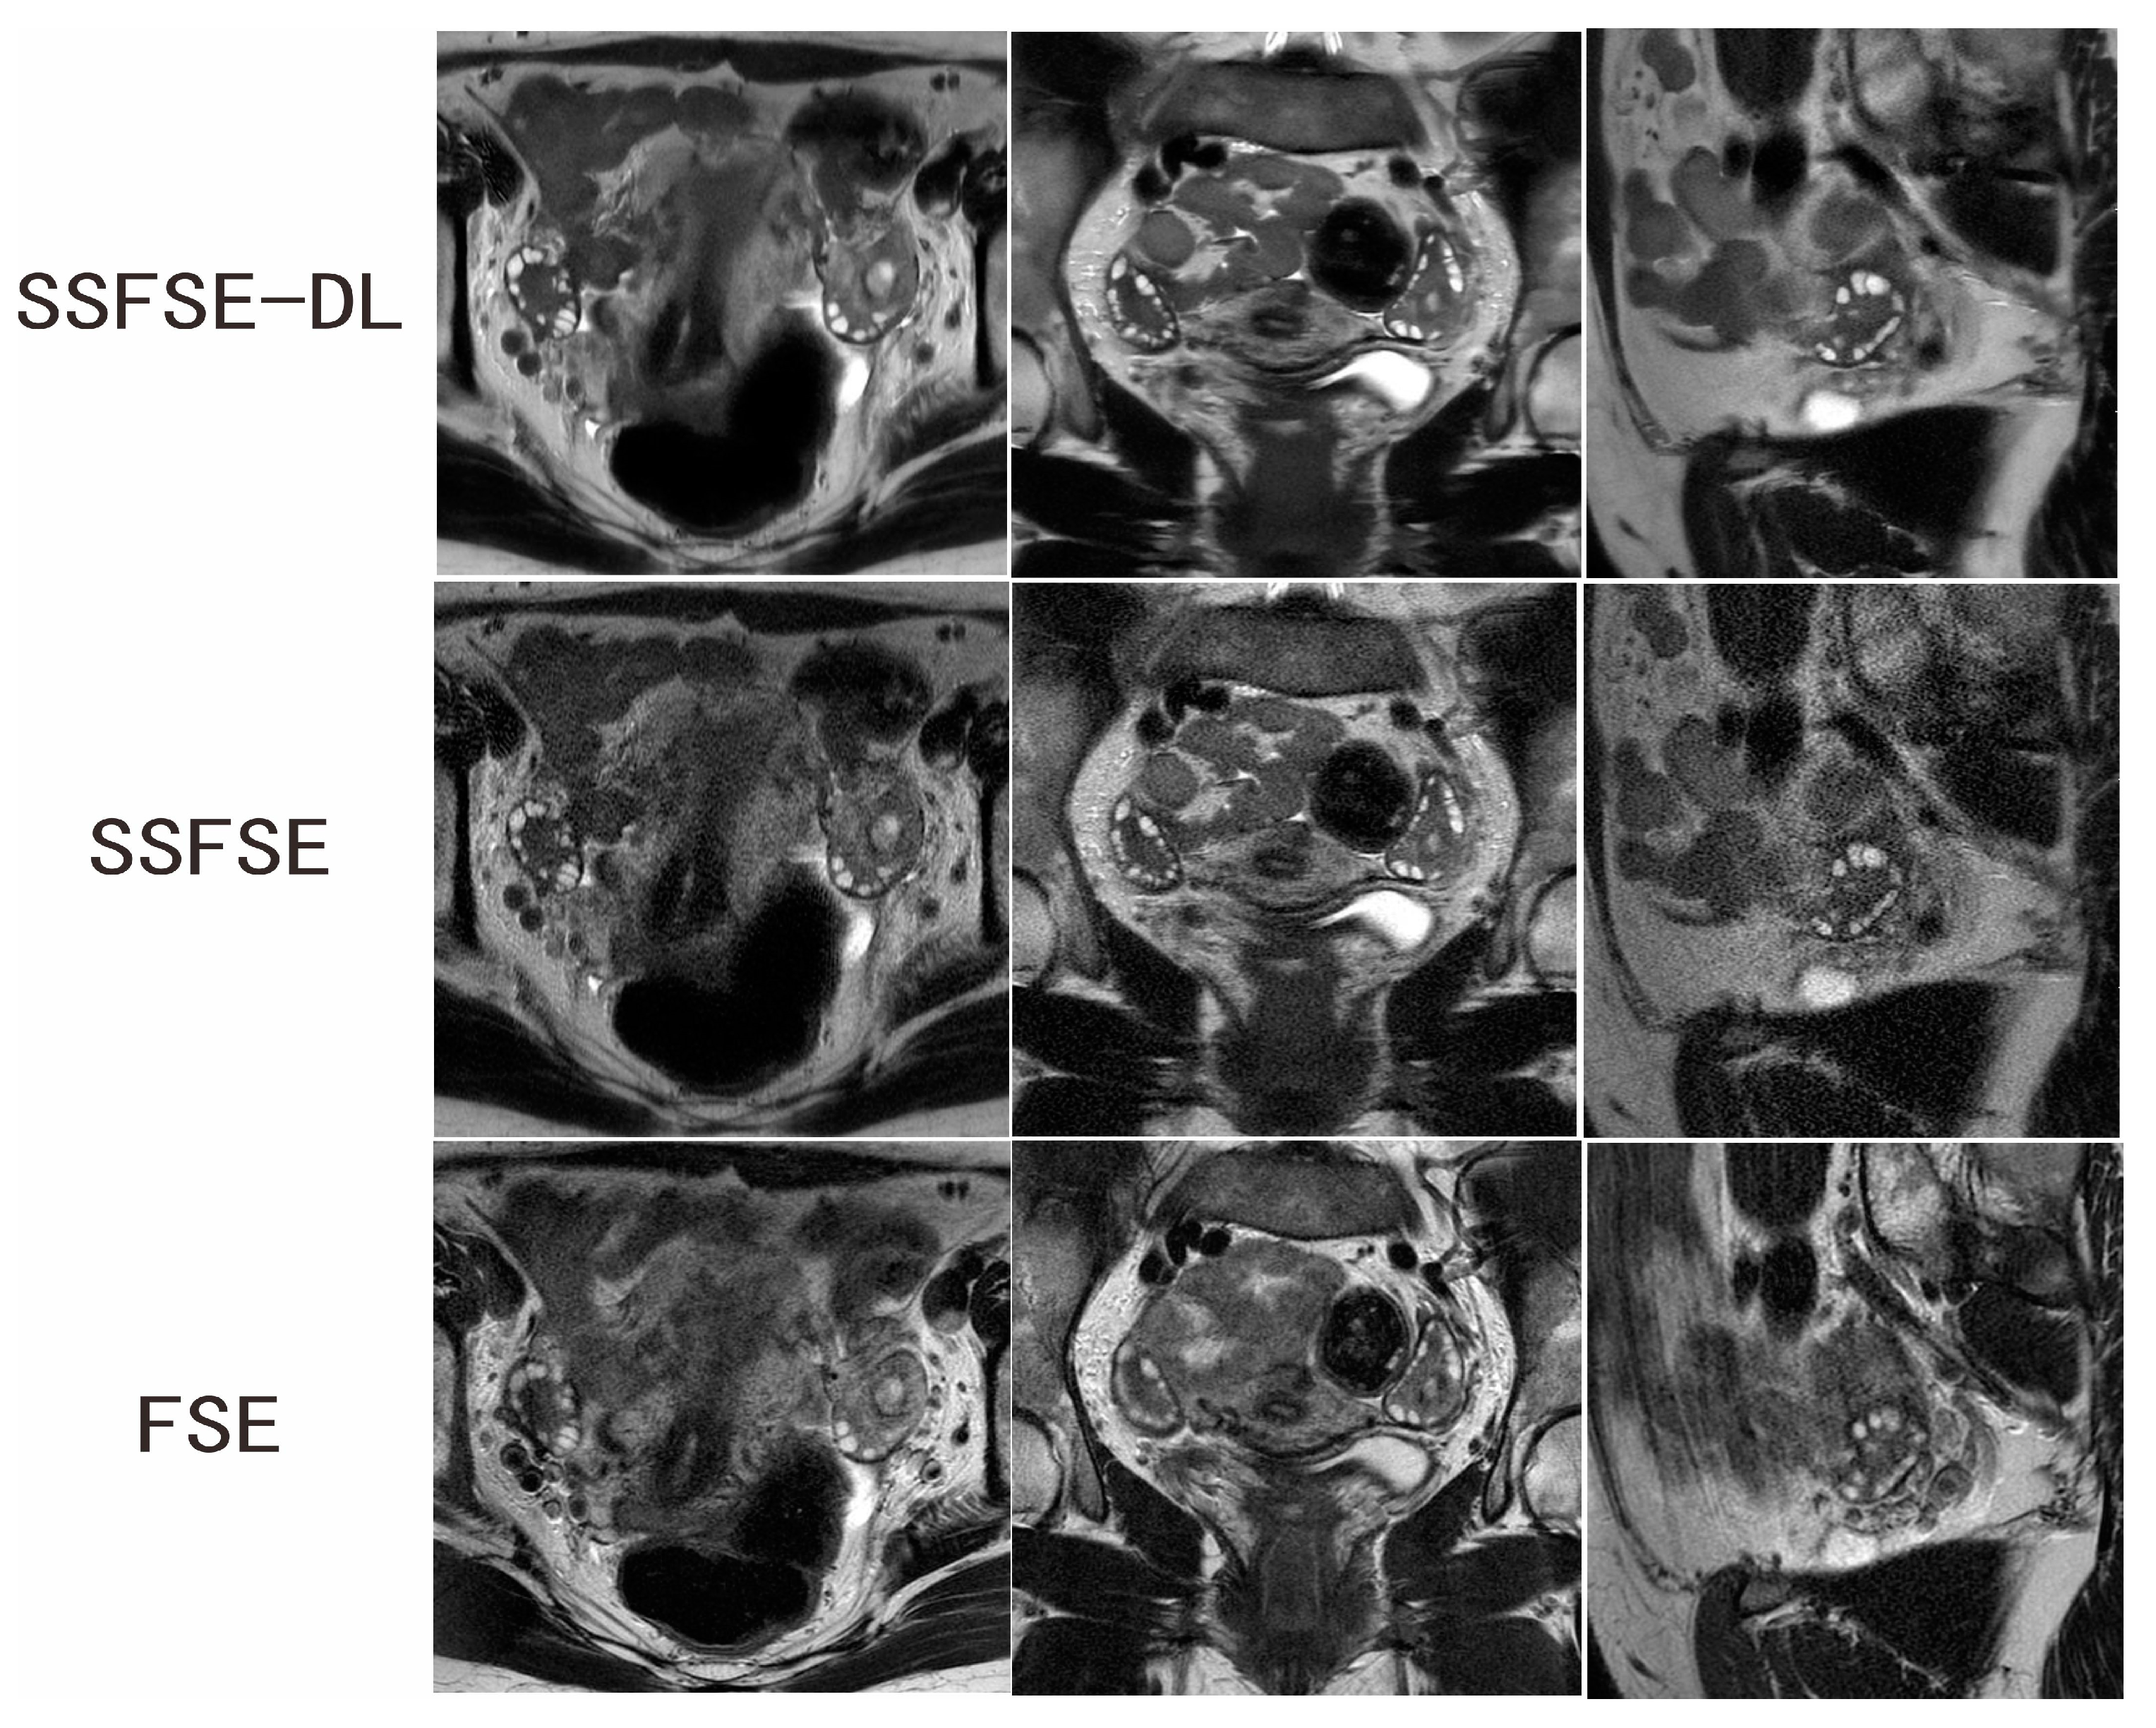

| Rated Feature | Observer | SSFSE-DL | SSFSE | FSE | SSFSE-DL vs. SSFSE | SSFSE-DL vs. FSE |

|---|---|---|---|---|---|---|

| Blurring artifacts | 1 | 2.600 ± 0.598 | 2.200 ± 0.834 | 1.950 ± 0.826 | p = 0.0117 | p = 0.0015 |

| 2 | 2.550 ± 0.510 | 2.050 ± 0.759 | 1.900 ± 0.788 | p = 0.0051 | p = 0.0022 | |

| Inter-observer agreement | 0.720 (0.463–0.976) | 0.591 (0.338–0.843) | 0.474 (0.165–0.783) | |||

| Subjective noise | 1 | 2.750 ± 0.550 | 1.500 ± 0.513 | 2.450 ± 0.605 | p = 0.0001 | p = 0.0277 |

| 2 | 2.650 ± 0.587 | 1.700 ± 0.571 | 2.250 ± 0.550 | p = 0.0001 | p = 0.0051 | |

| Inter-observer agreement | 0.789 (0.498–1.000) | 0.636 (0.352–0.921) | 0.664 (0.366–0.961) | |||

| Clarity of the follicles | 1 | 4.150 ± 0.745 | 3.700 ± 0.657 | 3.150 ± 0.875 | p = 0.0164 | p = 0.0003 |

| 2 | 4.400 ± 0.681 | 3.800 ± 0.696 | 3.200 ± 1.005 | p = 0.0051 | p = 0.0007 | |

| Inter-observer agreement | 0.671 (0.423–0.919) | 0.565 (0.245–0.885) | 0.536 (0.260–0.812) |